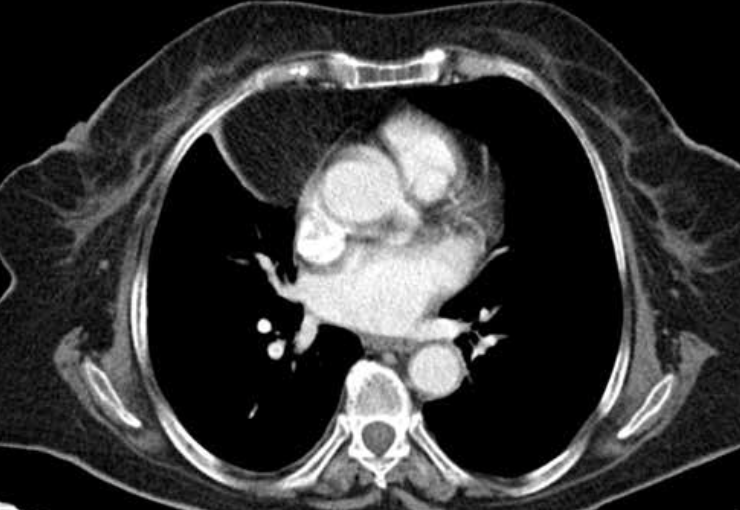

22

TC ventana mediastínica

Permite diferenciar las estructuras mediastínicas entre sí, pero el parénquima pulmonar aparece todo negro, sin apenas trama broncovascular.